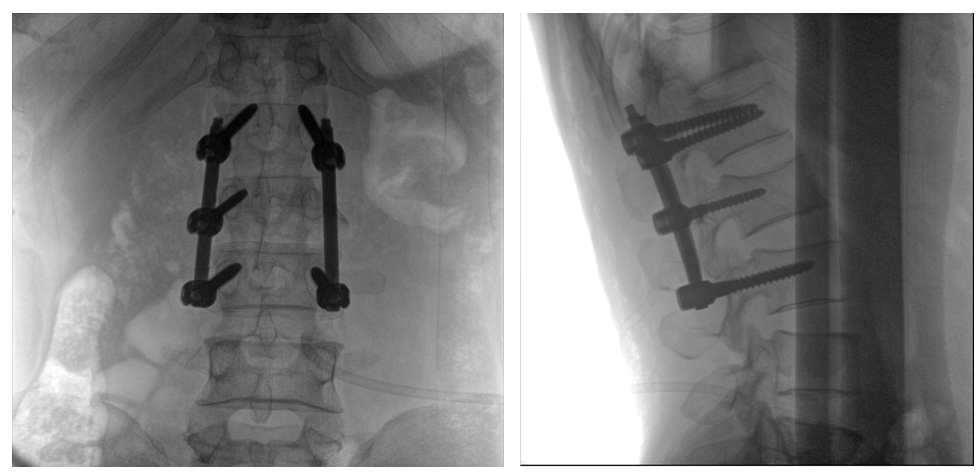

移動(dòng)式一體化C形臂全節(jié)段腰椎臨床影像

普愛(ài)醫(yī)療PLX119C大平板一體式C形臂采用30CM×30CM的平板探測(cè)器,在脊柱和長(zhǎng)骨骨折等骨科手術(shù)治療中,獲取更大視野、更清晰的骨折部位圖像,能夠有助于醫(yī)生在術(shù)中及時(shí)了解和評(píng)估骨折部位的對(duì)位、對(duì)線情況,且能進(jìn)行長(zhǎng)度和角度測(cè)量,為進(jìn)一步提高手術(shù)質(zhì)量提供強(qiáng)有力的支持。